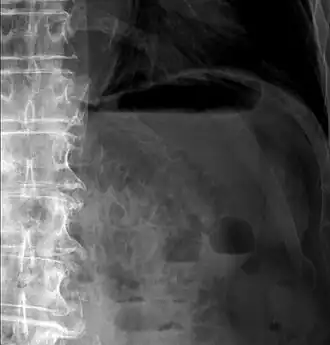

Pneumatosis intestinalis in computed tomography with intestinal ischemia. Lung window for better representation of the gas deposits in the intestinal walls. - Upright AP radiograph showing gas in the wall of the small bowel in the left upper quadrant indicative of pneumatosis intestinalis.